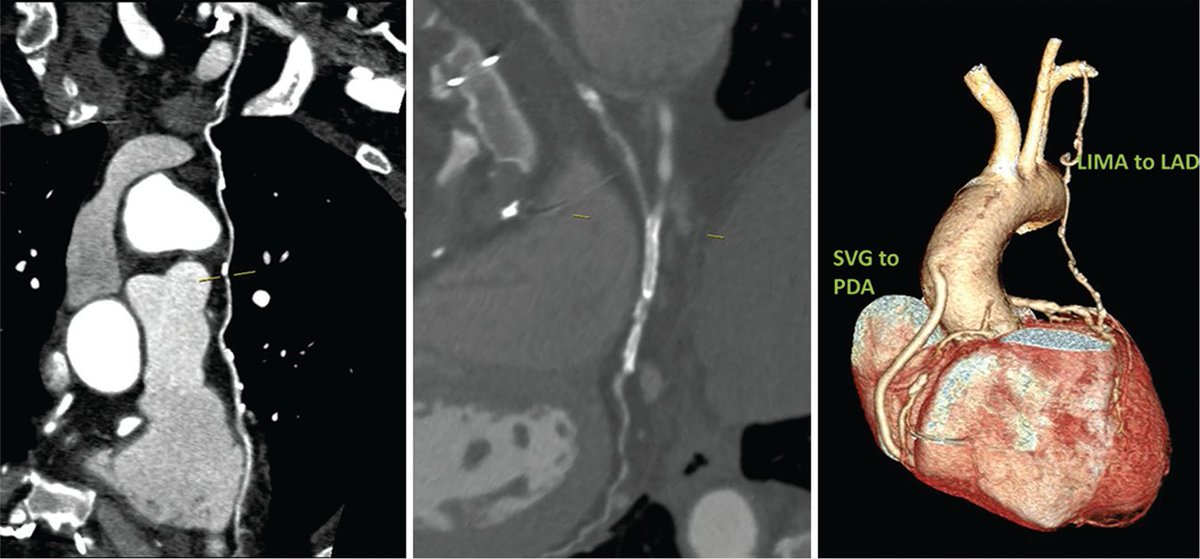

Read the article “Role of MDCT in Assessment of Long-term Graft Patency in Female Patients” which explaining CABG is a good non invasive alternative for CAG in post CABG women Learn more at ijcdw.org/role-of-mdct-i… #ijcdw #CABG #surgery #cardiology

Read the article “Role of MDCT in Assessment of Long-term Graft Patency in Female Patients” which explaining CABG is a good non invasive alternative for CAG in post CABG women